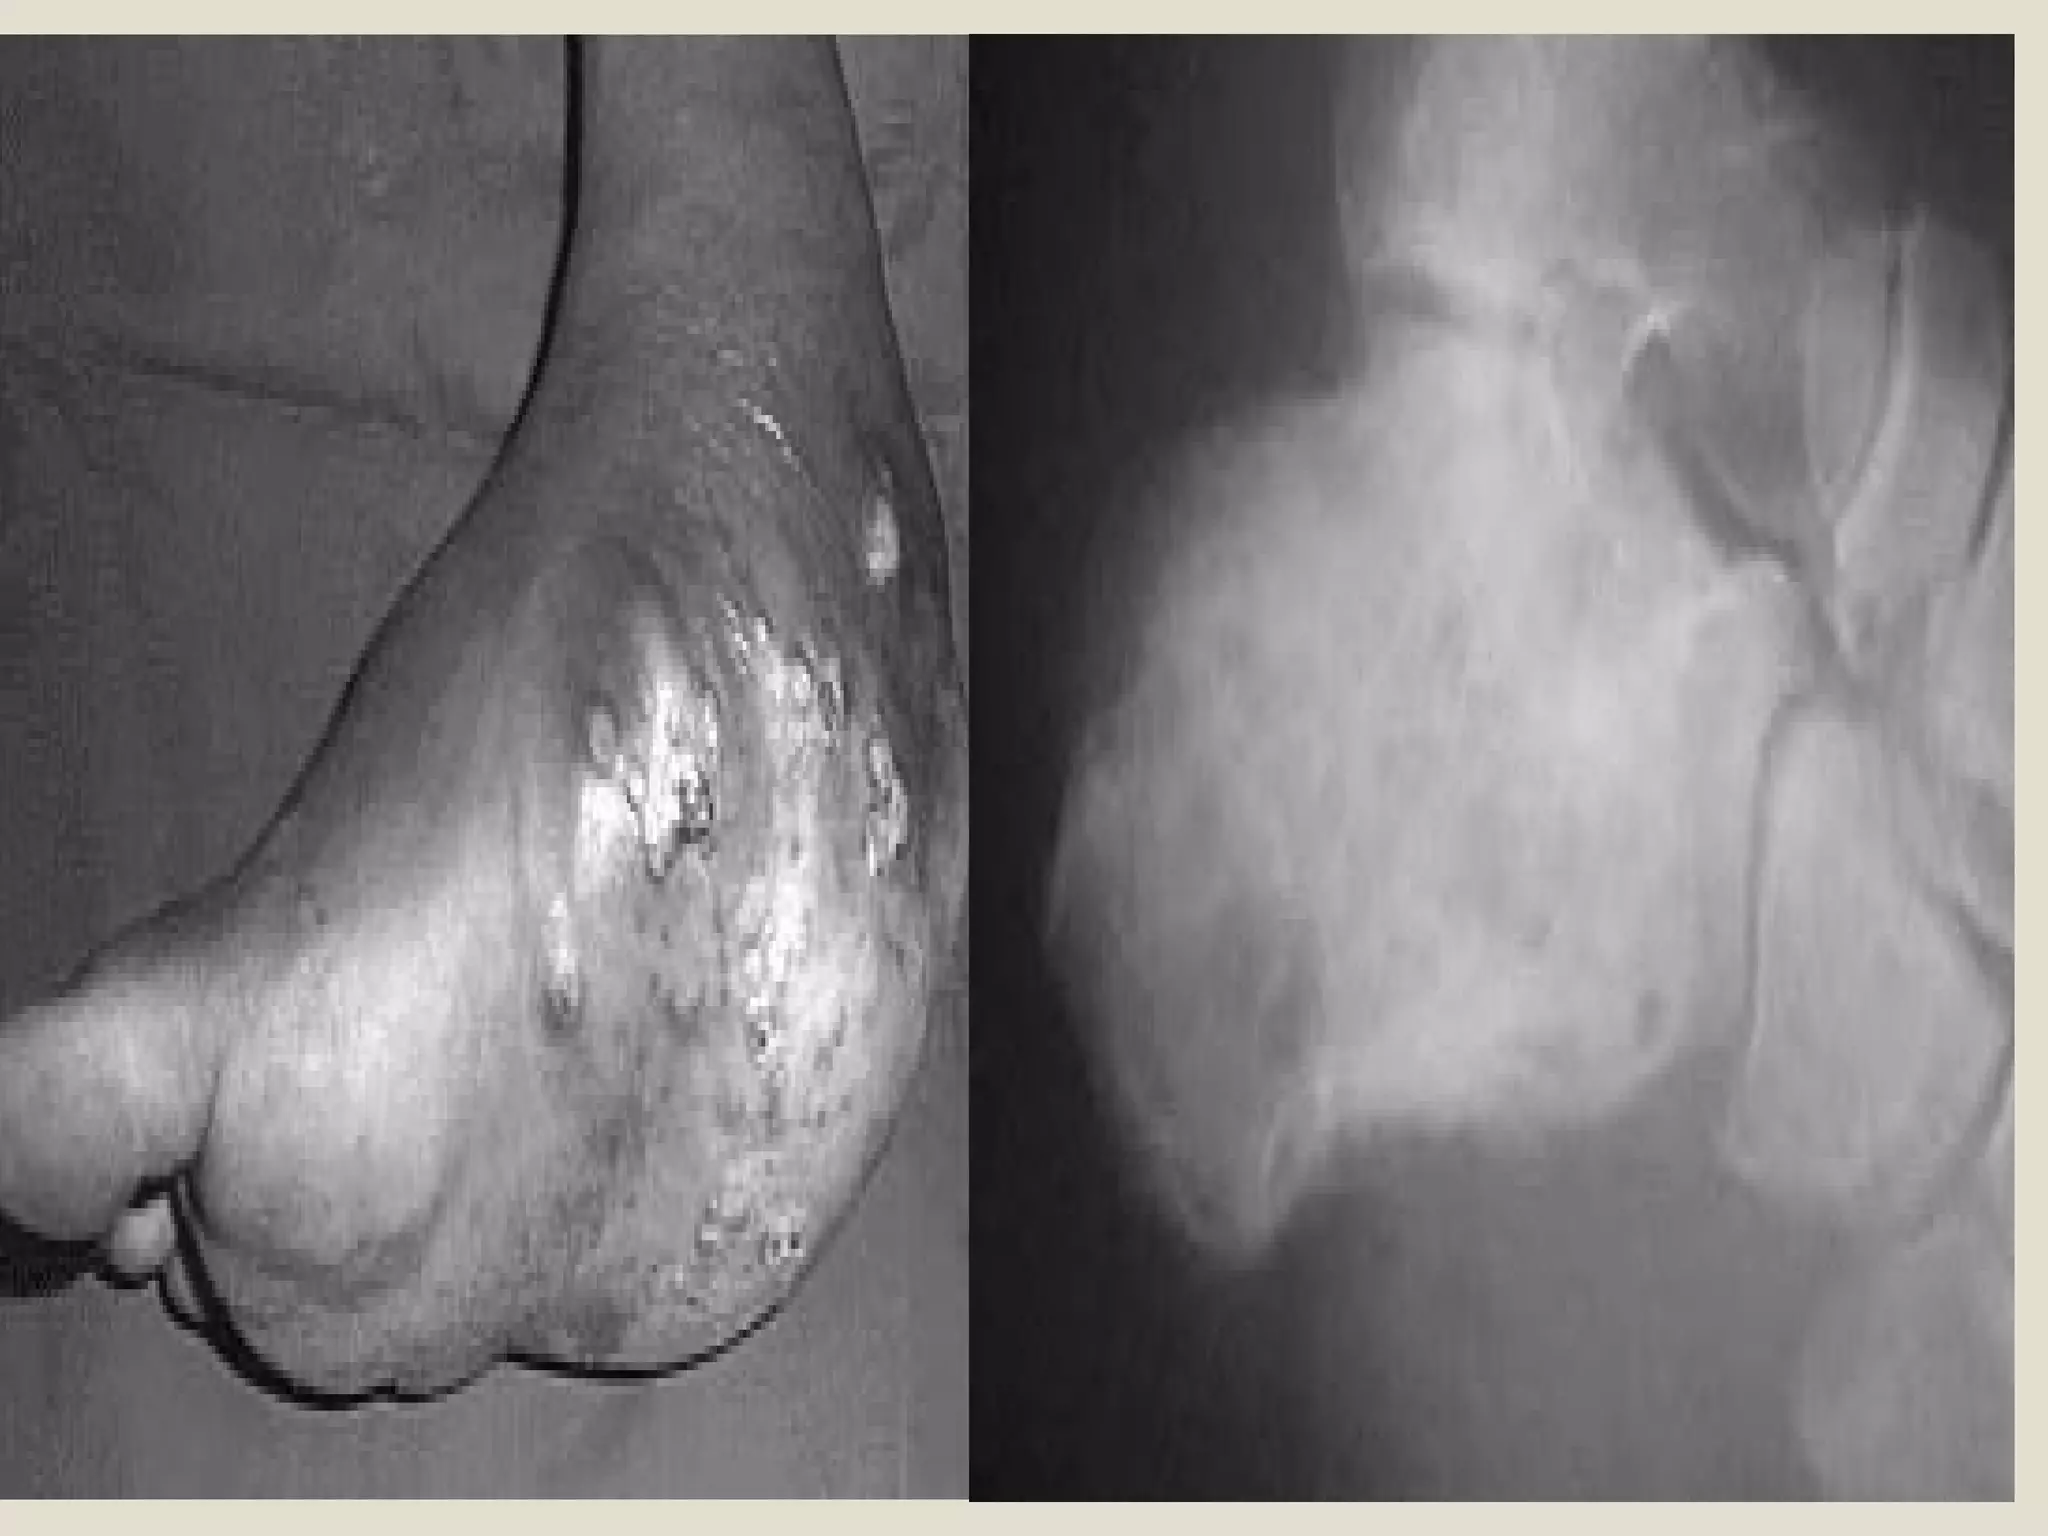

II. Subcutaneous Mycosis

Definition:

Chronic granulomatous infection, which

produce tumour-like lesion and sinus tract

formation, with the presence of granules

affecting foot, SC tissue, fascia and bone.

Etiology

(1) Bacteial:

◦ Actinomycotic (Actinomadura, Nocardia,

Streptomyces).

◦ The granules contain very fine delicate filaments.

(2) Fungal (Eumycotic):

◦ Most saprophytic fungi e.g. Madurella.

◦ The granules contain large coarse septated

hyphae.

◦ Usually the lesion has many openings.

Diagnosis

KOH preparation.

Bacterial: Fine branching filament.

Eumycotic: Coarse septated hyphae.

Treatment

Bacterial (Actinomycotic): Antibiotic.

Eumycotic:

◦ Amputation of the affected part.

◦ Antifungal agents e.g. Itraconazole,

Amphotericin B.